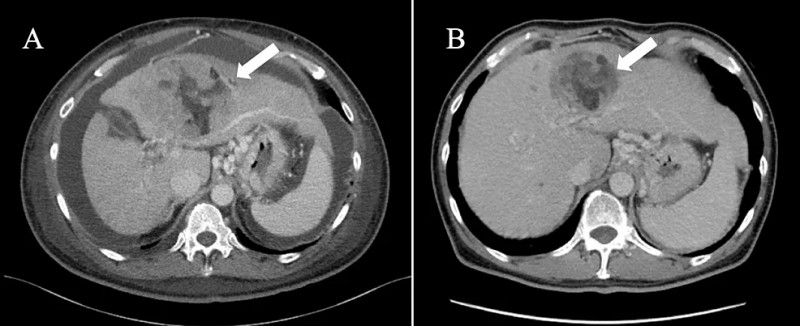

治疗后患者病情显著改善:前3个疗程结束,体能状态明显提升,腹胀症状有效缓解;第6个疗程结束后转至原医院复查,Child-Pugh分级已升至A级,CT扫描提示原发肿瘤及转移灶均缩小、腹水完全消失,符合实体瘤疗效评价标准(RECIST)1.1版的部分缓解(详见下图1B、2B);肿瘤标志物显著下降(维生素K缺乏诱导蛋白II恢复正常),白细胞总数及淋巴细胞比例亦恢复至正常水平。鉴于肝储备功能已显著改善,患者在完成第7个免疫联合治疗疗程后,顺利过渡至阿替利珠单抗联合贝伐珠单抗标准化疗。

▼经联合免疫治疗后横断面CT图像(病情有所改善)

▲图源“Cureus”,版权归原作者所有,如无意中侵犯了知识产权,请联系我们删除